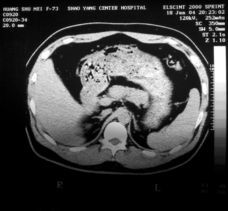

胰腺炎檢查7.B超與CT